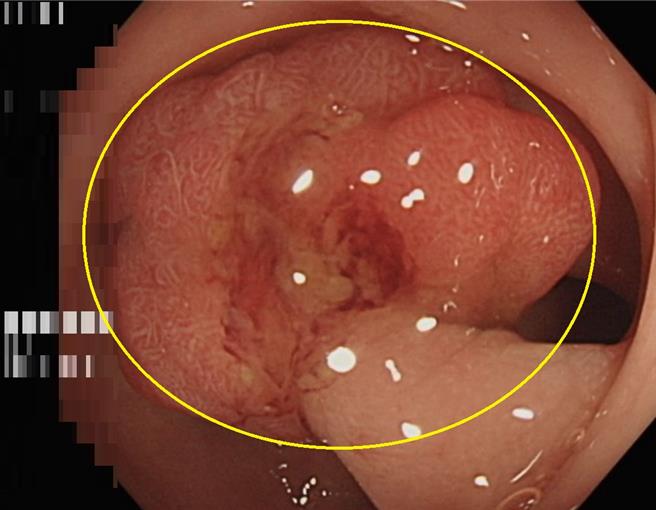

50歲林姓婦人經大腸鏡檢查影像報告瘜肉(黃圈處)屬於原位癌,幸好僅存在於表層黏膜尚未擴散。(長安醫院提供/馮惠宜台中傳真)

長安醫院肝膽腸胃科醫師許鈺銓表示,婦人因為糞便潛血篩檢陽性反應前來就診,經安排了大腸內視鏡檢查,最終發現在乙狀結腸處有1個1.5公分大小的瘜肉,當場進行了瘜肉切除手術,2周後回診病理報告確認該瘜肉為黏膜內腺癌,俗稱大腸原位癌。